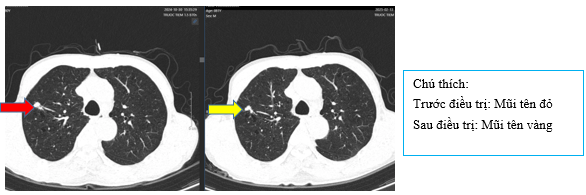

+ Chụp CT ngực sau điều trị

Hình 4:

So sánh phim chụp cắt lớp vi tính lồng ngực trước điều trị kích thước khối u thùy dưới phổi phải từ 40x30mm (mũi tên đỏ) sau điều trị giảm còn 26x20mm (mũi tên vàng)